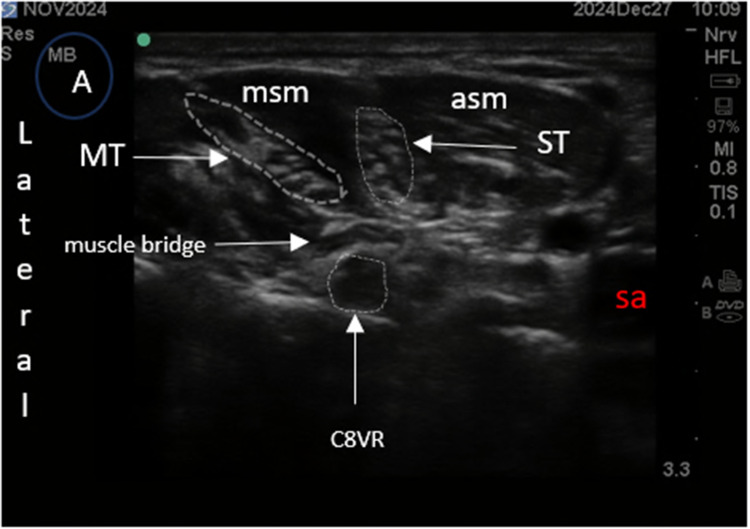

Methods: We developed a novel ultrasound-guided regional anesthesia technique-the Single-entry Selective Trunk Block (S-SeTB)-which targets the superior trunk (ST), middle trunk (MT), and C8 ventral ramus (C8VR) with local anesthetic diffusion to the inferior trunk (IT). The procedure uses one skin entry point to deliver three injections and is combined with a superficial cervical plexus (SCP) block using the same entry and ultrasound plane. Over 600 procedures were performed in field hospitals operated by the International Committee of the Red Cross, with observations documented.